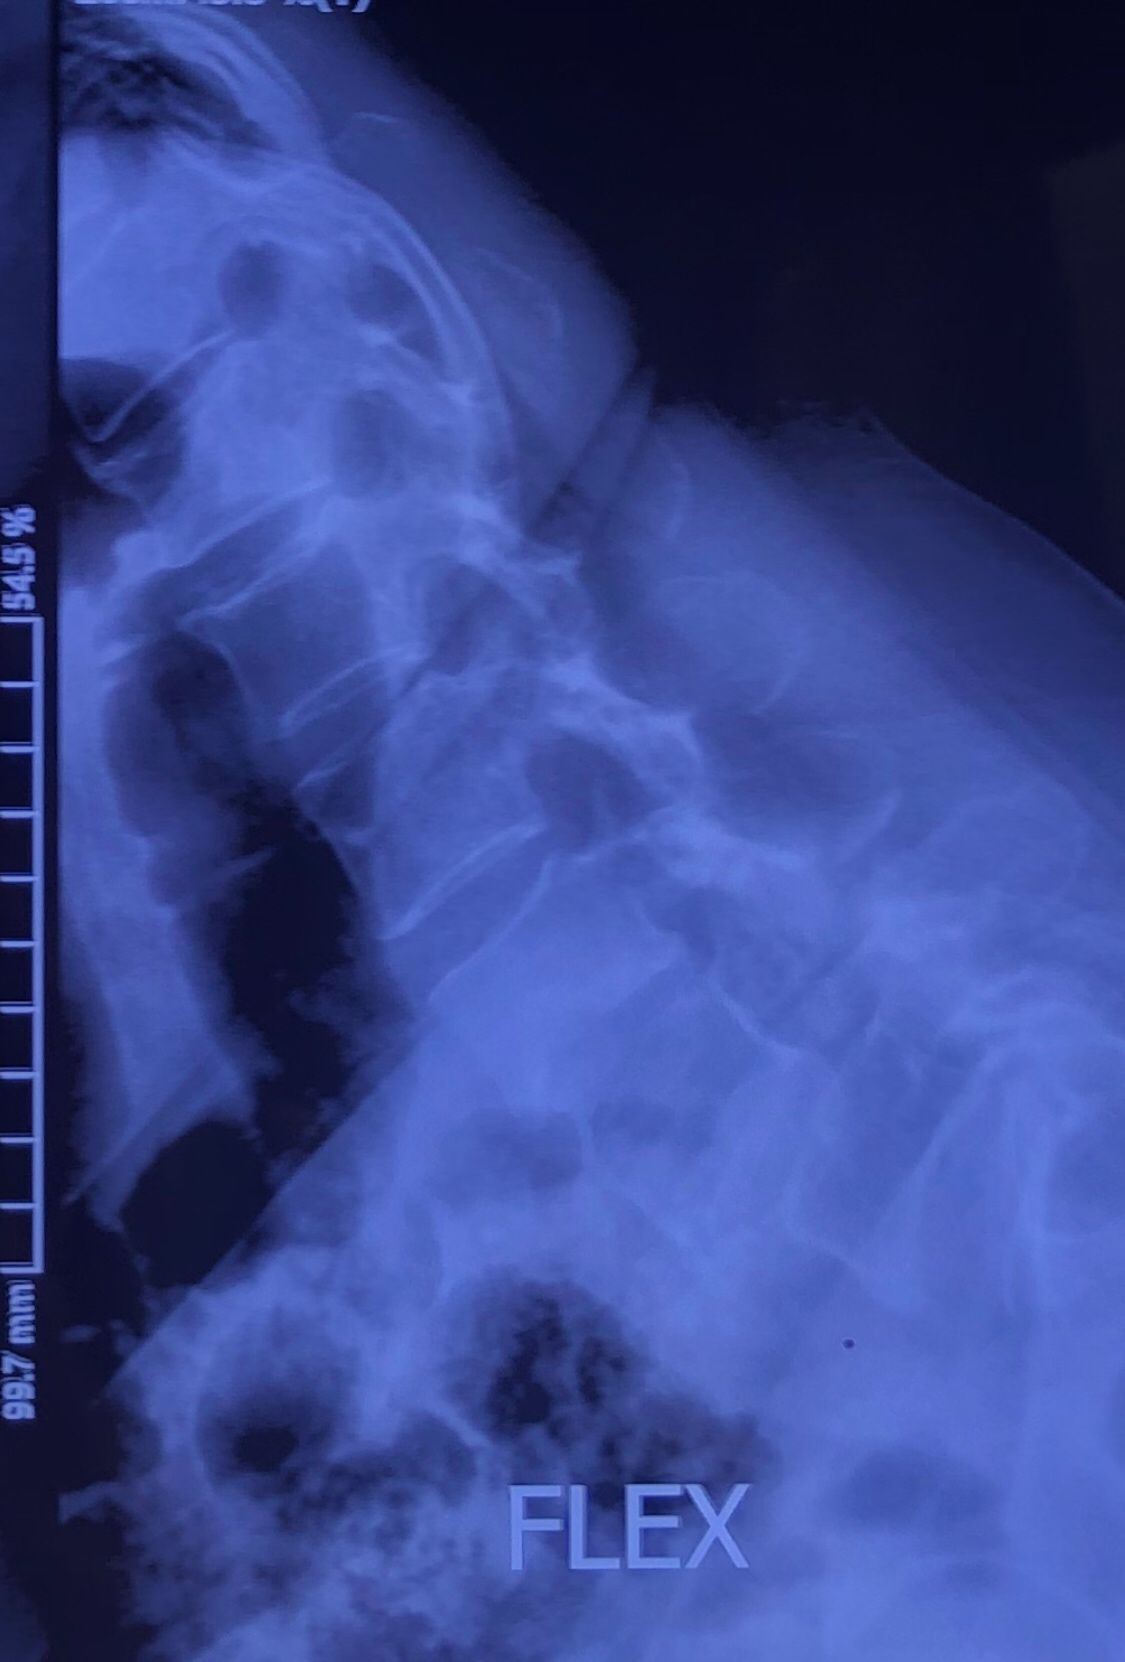

Since I’ve noticed instability in some segments I asked for dynamic L/S x ray:we see mild L4 ant listens due to DjD/DDD. There is not any pars defect.

Is ant listhesis of L4 unstable or stable?